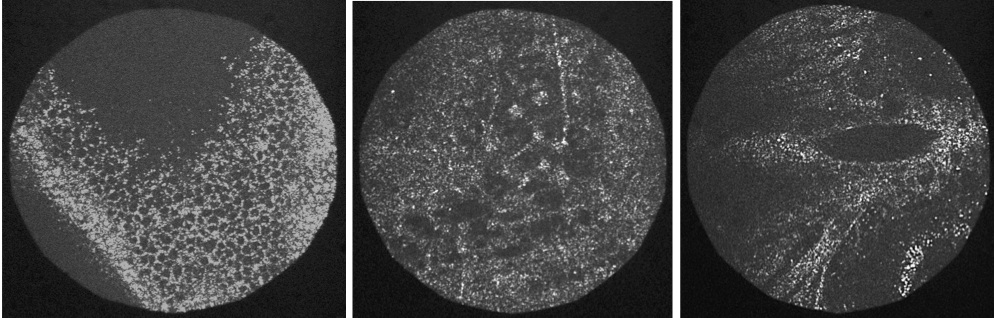

Pour simuler les conditions d’un oeil in vivo, un écran de phase introduisant des aberrations typiques d’un oeil a été placé dans un plan pupille (équivalent de la cornée). Il est déplacé par des moteurs afin de simuler les mouvements de l’oeil en amplitude et en vitesse (330 microns/s sur 2 mm).

La correction par optique adaptative en double passage permet à la fois de :

On peut ainsi constater sur une feuille de papier le gain apporté par l’optique adaptative sur des images OCT grâce à la correction des aberrations.

Des images OCT de rétine corrigées par OA sont en cours d’acquisition.